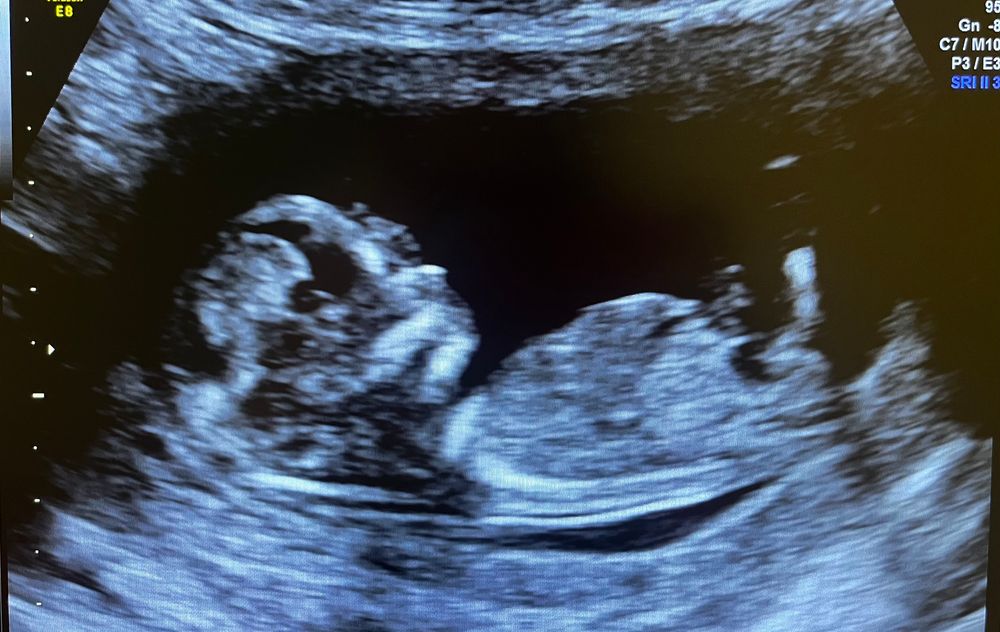

Девочки добрый день , наконец получили первое фото с нашего узи. Рада буду любому полу) но интересно кто же будет , как думаете ?

Полового бугорка на фото нет, поэтому все голосовать будут пальцем в небо.